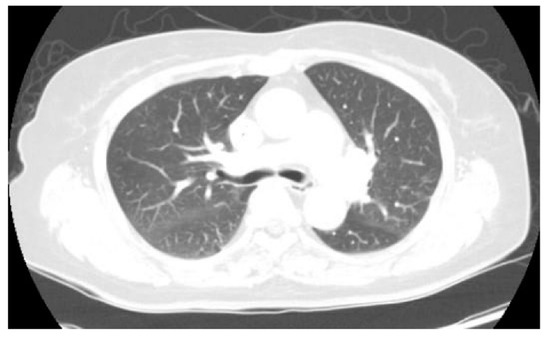

Figure 1. A chest X-ray was performed at admission, showing scattered nodular opacities in the left lung upper lobe and right lung lower lobe, which indicated a central area of excavation (arrows). 18F-fluorodeoxyglucose positron emission tomography/computed tomography (18F-FDG PET/CT) has increasingly been used to manage cancers and infections [1,2,3]. Since FDG uptake is directly representative of glucose metabolism, it can increase in inflammatory cells as well as tumor cells. Long-term indwelling central venous catheters are necessary for treating cancer patients due to chemotherapy. They depend on their central venous catheters daily, which could predispose a significant risk of complications such as catheter-related bloodstream infection (CRBSI) [4,5,6]. CRBSI can be complicated by metastatic infectious foci associated with a high morbidity and mortality rate, which should require prolonged systemic antimicrobial treatment [7]. The significant complication of CRBSI is septic thrombosis, with a prevalence of 15~24% [8,9]. The clinical diagnosis of septic foci is critical but may be difficult to establish due to the challenge of determining between sterile catheter-related thrombosis and actual septic thrombosis. Additionally, symptoms are often non-specific, and there is a lack of sensitivity to conventional diagnostic imaging techniques. Only a few studies investigated that 18F-FDG PET/CT can find the infectious foci, demonstrating it as an accurate imaging modality for metastatic foci [10,11,12]. Here, we would like to report a female patient with a Staphylococcus aureus-implantable venous access catheter infection in which 18F-FDG PET/CT determined unsuspected septic pulmonary emboli. A 71-year-old female patient with known ovarian cancer visited our hospital to receive the 4th adjuvant chemotherapy. She was treated with total abdominal hysterectomy, bilateral salpingo-oophrectomy and omentectomy 6 months ago. She also had a history of central venous catheterization by the right internal jugular vein approach, terminating at the junction of the superior vena cava and right atrium. The adjuvant chemotherapy was already performed three times as the regimen of Paclitaxel plus Carboplatine after surgery. At admission, she presented no clinical symptoms such as fever, cough, sputum, dyspnea, or chest pain. However, the chest X-ray showed scattered nodular opacities in the left lung upper lobe and right lung lower lobe, suspicious of metastatic nodules (Figure 1). Her blood test showed unexplained leukocytosis (12.58 × 103/μL), elevated D-dimer (9.46 mg/L), and a tumor marker such as CA-125 (41.89 U/mL). 18F-FDG PET/CT was performed 2 days after admission, observing abnormal FDG uptake in the chemo-port catheter, right pectoralis muscle, and 1st costochondral junction (Figure 2a–d). PET/CT also revealed hypermetabolic nodules scattered throughout both lungs, consistent with septic embolism (Figure 2e). In the evening of the day of the PET/CT examination, the patient presented swelling, redness, and some discomfort at the catheter insertion site. The catheter was removed the next day, isolating methicillin-sensitive Staphylococcus aureus from the catheter tip and peripheral vein. A transthoracic echocardiogram and fundus examination, which were performed to evaluate possible metastatic infections such as infective endocarditis or endophthalmitis, were reported as normal. She was treated with intravenous cefazolin for 4 weeks followed by oral linezolid for 1 week, recovering uneventfully without relapse. She was also treated with rivaroxaban 15 mg for 3 weeks and was diagnosed with pulmonary thromboembolism. After 2 months, a follow-up chest CT showed that the pre-existing multiple nodules in both lungs had disappeared (Figure 3).

Figure 2. 18F-FDG PET/CT images (a) showed abnormal FDG uptake in the chemo-port catheter (b), right pectoralis muscle (c), and the anterior thoracic wall around the first costochondral junction, consistent with an inflammatory/infectious process (d). Lung window setting image, showing multiple cavitating hypermetabolic nodules in both lungs consistent with septic pulmonary emboli (e). According to these findings, the patient was suspected of having catheter-related bloodstream infection and septic pulmonary emboli.